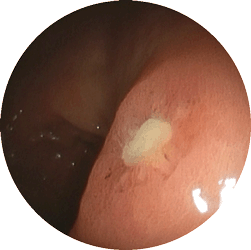

十二指腸潰瘍2

十二指腸潰瘍

嘔気(吐き気)と鈍い痛みで

来院

内服薬1ヶ月で治癒